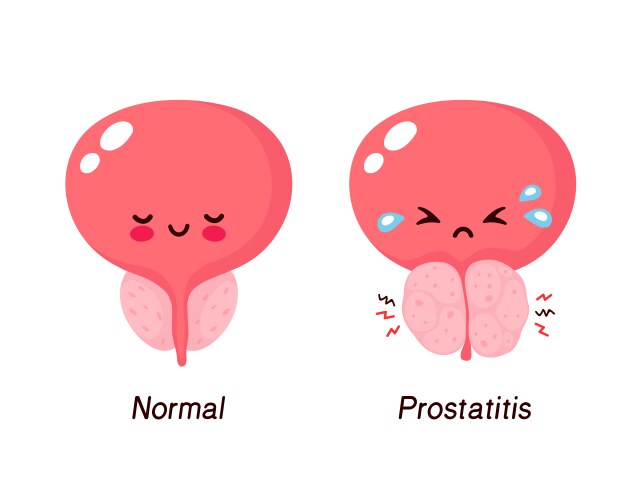

- Prostatitis

- Disease

- Swelling

- Inflamed

- Pain